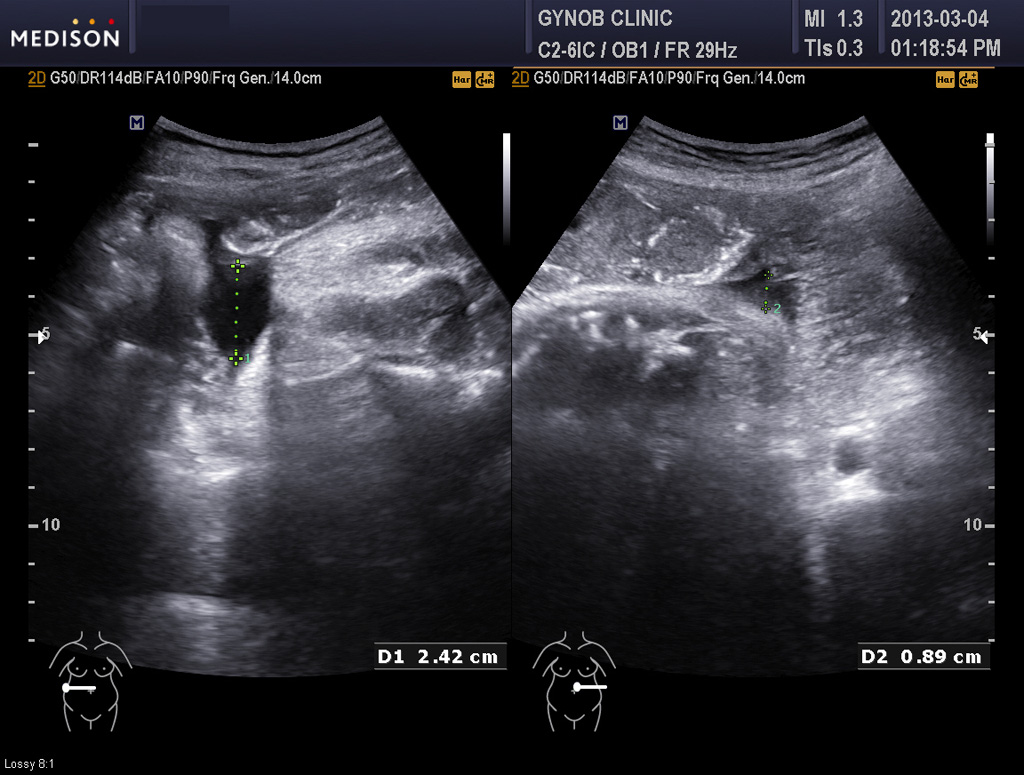

한분은 먼저 진찰에서도 조금 그렇기는 했지만 며칠 전 초음파 검사에서 양수양이 상당히 적은 양수 과소증(양수 점수인 AFI가  5점이하 수준)으로 판단되어 아기의 건강이 다소 위협 받고 있는 상황일 가능성이 있어서 이송한 경우였습니다.

다행히 아기 발육은 괜찮은 편이었지만 양수의 양은 아기의 건강을 나타내주는 지표 중의 하나이기도 하고 또 양수가 적으면 진통 중 탯줄이 눌리거나 하여 태아 곤란증에 빠지기도 해서 양수양이 너무 적은 것은 그리 좋은 신호는 아닙니다.

그래서 양수 과소증이 발견되면 태아의 성장을 감안하여 결정하기는 하지만 대체로 빨리 출산을 하는 것이 원칙이라 유도분만을 하게 됩니다.

아래 사진은 그 산모분의 산전 진찰시 초음파 사진인데 위는 양소 과소증을 나타내 주는 사진이고 아래는 태아 방광의 사진입니다.